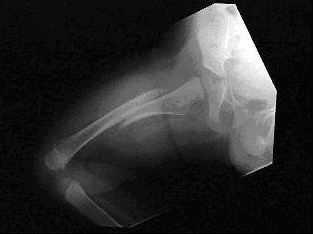

A 2-year-old boy is brought to the emergency room by his parents because of limping. His parents report that he was well until yesterday, when he fell in the bathtub. Since then, he has been limping and refusing to bear weight on his right leg. A radiograph of the right femur shows a displaced transverse fracture of the shaft of the femur without soft tissue changes. The child's leg is immobilized and stabilized. Complete blood count and coagulation studies are within normal limits.

A radiograph of a femur showing a displaced transverse fracture of the shaft of the femur without soft tissue changes

This patient has sustained a closed fracture of the femur shaft with no apparent bleeding into the thigh. Femoral shaft fractures result from high-energy trauma. In young children, one must always consider the possibility of abuse because approximately 70% of femur fractures are nonaccidental (i.e., inflicted). The patient is stable and immobilized and, at this point in management, requires a skeletal survey to identify other possible fractures and evaluate for potential abuse.